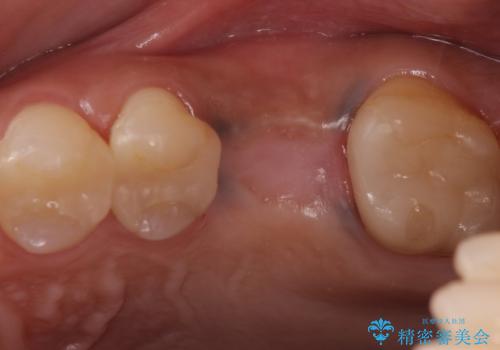

良い位置に良い方向でインプラントを埋入することができました。

手前の歯の虫歯もセラミックインレーで精度よく治療を行いました。